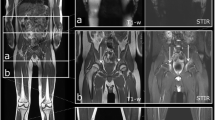

There were five patients with a final diagnosis of rheumatoid arthritis, two with and three without osteitis in MRI, involving ten bones in total. VBMI correctly identified osteitis in both positive patients (seven true-positive, two false-negative, and one false-positive bone) and correctly showed the absence of osteitis in the three negative patients. One patient with infectious arthritis showed osteitis in MRI and VBMI, however, VBMI identified only two out of four affected bones. The bone marrow changes of another patient with bone infarction was detected by both MRI and VBMI. The other patients with the final diagnosis of crystal arthropathy showed no BME in either of the modalities. The false-negative results in VBMI occurred as discreet BME of the proximal phalanx 5 of the tarsus (patient No. 2), the intermediate phalanx 4 (patient No. 3), and the distal fibula and tibia (patient No. 11) in MRI. There was one false-positive detection in the metatarsal head (patient No. 2), as shown in Fig. 1. However, on the patients’ level, there were no false-positive or false-negative detections using VBMI. This means, each patient showing BME in MRI was detected by VBMI and each patient without BME in MRI was negative using DECT, respectively.

Left foot of patient No. 2 (seropositive RA). CT: normal CT image at 135 kV, VBMI: corresponding VBMI image, MRI: corresponding fat-saturated T2 sequence – multiplanar reformatted VBMI shows a good correlation to the corresponding MRI with regard to the identification of BME at the first, second, and fifth metatarsophalangeal joint (arrowheads). However, in MRI, there are artifacts due to incomplete fat saturation in the second and third toes (arrows). The corresponding CT image appearance is normal

Figures 1, 2, 3, and 4 provide examples of true-positive, false-positive, and false-negative findings.

Right foot of patient No. 2 (seropositive RA). CT: normal CT image at 135 kV, VBMI: corresponding VBMI image, MRI: corresponding fat-saturated T2 sequence – VBMI displays the BME in the fourth metatarsal head (arrowheads) with erosions and cysts in CT. In the first metatarsal head, VBMI is false positive compared to MRI (arrow)